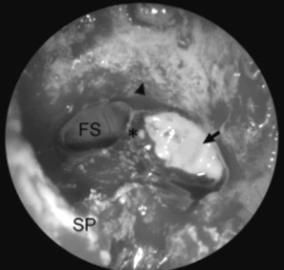

急性咽炎CT臨床表現檢查口咽及鼻咽黏膜呈急性充血,齶弓、懸雍垂水腫,咽後壁淋巴濾泡和咽側索也見紅腫。細菌感染者,間或在淋巴濾泡中央出現黃白色點狀滲出物。頜下淋巴結腫大並有壓痛。嚴重者,可累及會厭及的會厭襞,還可引起發生水腫。中耳炎、鼻炎、鼻竇炎、喉炎、氣管炎、支氣管炎及肺炎等。